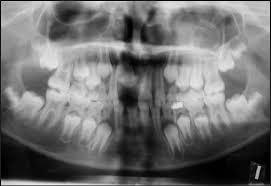

We provide Panoramic dental x-ray services which use a very small dose of ionizing radiation to capture the entire mouth in one image. It is commonly performed by dentists and oral surgeons in everyday practice and may be used to plan treatment for dentures, braces, extractions, and implants.